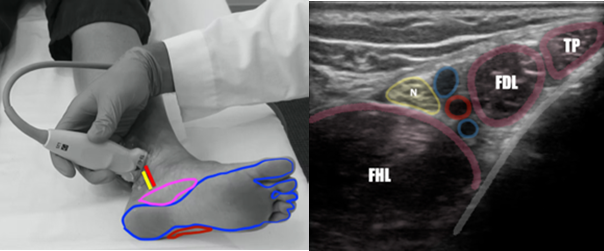

The posterior tibial nerve provides sensory innervation to the majority of the plantar foot, sparing the most medial and lateral aspects which are innervated by the saphenous and sural nerves, respectively. (Figure 1) The posterior tibial nerve is easiest identified just posterior to the medial malleolus in close proximity to the posterior tibial artery (Figure 1). At this location, both the posterior tibial artery and nerve lie between the flexor hallucis longus and flexor digitorum longus tendons as depicted by ultrasound imaging. (Figure 1)

Figure 1. Identification of the Posterior Tibial Nerve in the Distal Ankle. Left: Position of tibial nerve and artery (red/yellow lines) in location of potential blockade and nerve distribution of posterior tibial block (blue), with saphenous nerve distribution (pink) and sural nerve distribution (red). Right: Sonographic anatomy of the PT nerve at the level of the medial malleolus. (FHL=flexor hallucis longus, N=posterior tibial nerve, Red circle= posterior tibial artery, FDL=flexor digitorum longus tendon, TP=tibialis posterior tendon). Image courtesy of Dr. Ryan Barnes